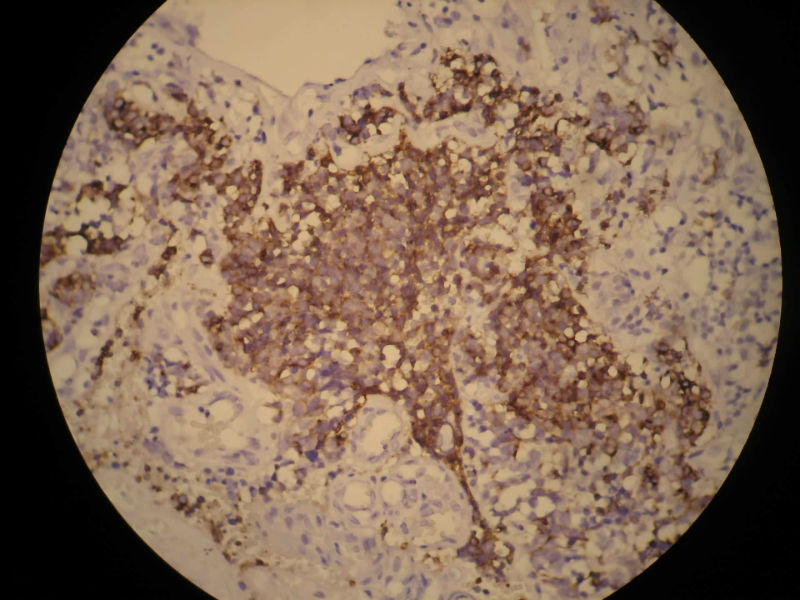

患者,M50Y,左侧肢体乏力半个月,肌力2级

MRI示右顶叶和小脑占位性病变,增强强化明显

术中见鱼肉样质脆,血管丰富,边界不清,部分囊性变,分块切除

大体:碎组织,4.2*3.5*2cm,呈鱼肉状,质嫩软。其间可见少量灰白组织,质韧。

Based on histology and immunohistochemistry, metastatic neuroendocrine carcinoma needs to be ruled out. I suggest TTF-1 stain. Also pay attention to nuclear morphology at high power view and see if it fits small cell carcinoma. It doesn't have to be a primary CNS tumor just because the border appears infiltrative.

谢谢Dr.mjma和楼上各位的指导。形态学符合小细胞癌。我们加做TTF-1,CD56和NSE,下周有结果。